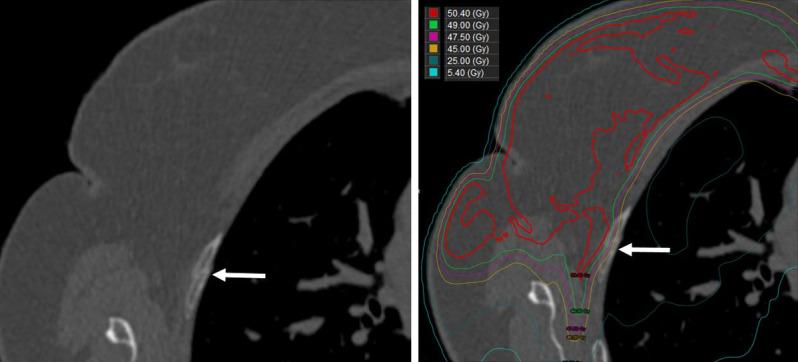

From a prospective database, we identified 225 patients treated with proton therapy between 2012 and 2020 (223 women; 2 men). Clinical and dosimetric data were extracted, the cumulative incidence method assessed rib fracture rate, and Fine-Gray tests assessed prognostic significance of select variables. In-field rib fracture was defined as a fracture that occurred in a rib located within the 10% isodose line. Out-of-field rib fracture was defined as a fracture occurring in a rib location outside of the 10% isodose line.

Of the patients, 74% had left-sided breast cancer; 5%, bilateral; and 21%, right-sided. Dual-energy x-ray absorptiometry scans showed normality in 20%, osteopenia in 34%, and osteoporosis in 6% (test not performed in 40%). Additionally, 57% received an aromatase inhibitor. Target volumes were breast ± internal mammary nodes (IMNs) (16%), breast and comprehensive regional lymphatics (32%), chest wall ± IMNs (1%), and chest wall/comprehensive regional lymphatics (51%). Passive-scattered proton therapy was used for 41% of patients, 58% underwent pencil-beam scanning (PBS), and 1% underwent a combination (passive scattering/PBS), with 85% of patients receiving a boost. Median follow-up was 3.1 years, with 97% having >12-month follow-up. The 3-year cumulative in-field rib fracture incidence was 3.7%. Eight patients developed in-field rib fractures (1 symptomatic, 7 imaging identified) for a 0.4% symptomatic rib fracture rate. Median time from radiation completion to rib fracture identification was 1.8 years (fractures were identified within 2.2 years for 7 of 8 patients). No variables were associated with rib fracture on univariate analysis. Three fractures developed outside the radiation field (0.9% cumulative incidence of out-of-field rib fracture).